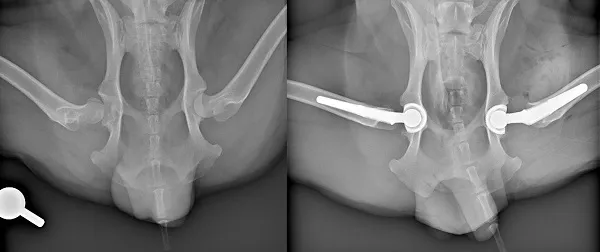

xrays of dog before and after double hip replacement surgery

Xrays showing Theo's hips before and after two hip replacement procedures to replace his misshaped femoral head and hip sockets with prosthetics

Theo is now living pain-free and no longer requires non-steroidal anti-inflammatory drugs. His owners report that his activity levels have markedly improved since surgery, as have his general mobility and energy levels. X-ray following surgeries shows two prosthetic femoral heads sitting correctly in prosthetic ‘cup’ implants.